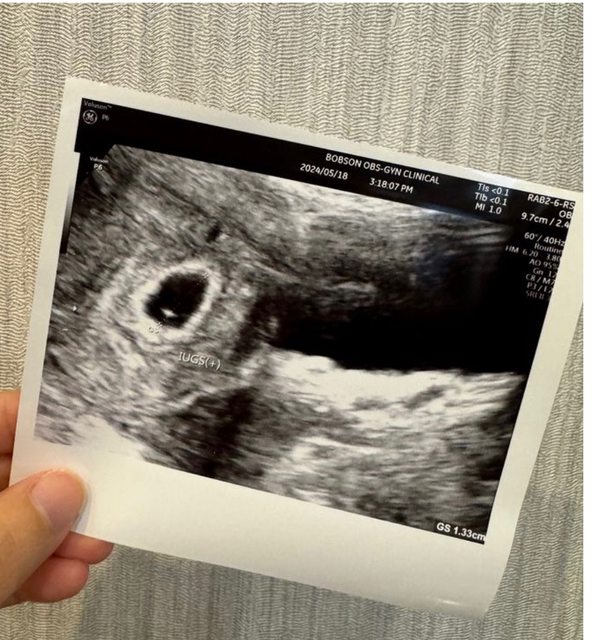

各位爸爸媽媽好, 我上一次月經第一天是3/25, 5/4去照超音波看到約0.56的胚囊, 5/18去照超音波看到約1.33的胚囊,但還沒看到胚胎,按照孕期計算這週應該是第七週, 但醫生說可能才五週多一點,醫生說下週一定要看到胚胎。 請問爸爸媽媽誤差的兩週是正常嗎, 我好緊張喔QQ https://i.imgur.com/86HaV2s.jpeg

n870881 : 我第一次照也是誤差約兩週喔 過兩週照到心跳就校正 05/22 19:57

n870881 : 回歸了 現在10週了寶寶很健康~ 05/22 19:57

lalatwo : 我第二次看診也是應該8週但照出來才6週,後來一週後 05/22 20:08

lalatwo : 回診照到,後續大小也慢慢追上,目前13週已經跟app 05/22 20:08

lalatwo : 推估時間一樣 05/22 20:08

qiori : 我第一胎也是差兩週,醫生說就比較晚受孕而已,小 05/22 22:35

qiori : 孩都已經6歲,放鬆心情吧 05/22 22:35